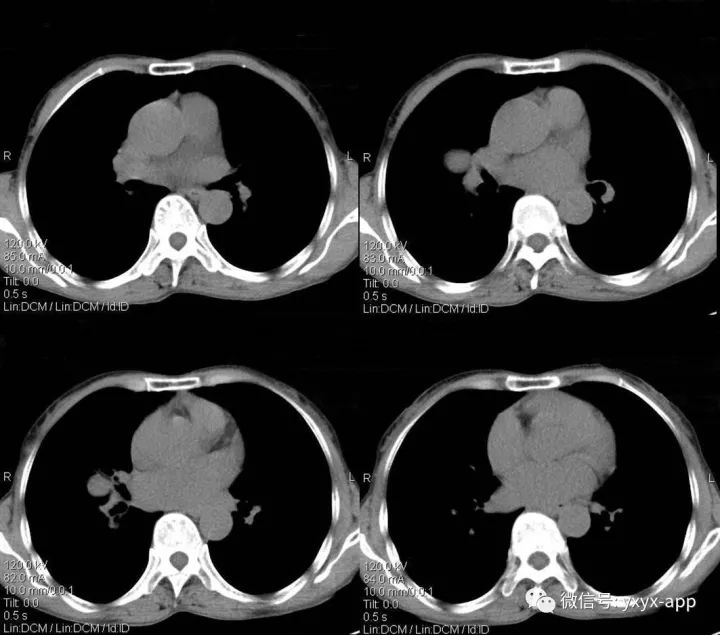

肚肚丫头:右肺门结节影,边界清,密度尚均匀,增强扫描动脉期,病变呈轻度强化,静脉期强化明显(与血管相当),病灶部分与支气管相贴。纵隔未见肿大的淋巴结。考虑与血管相关的良性病变可能。1.硬化性血管瘤;2. 巨淋巴结增生不除外

1.病灶为圆形或类圆形,边缘光滑,无毛刺,少数可有分叶,约70%病灶直径小于3cm。肿瘤无包膜,钙化率可达40%以上,可有囊变。

2.CT平扫病灶密度较均匀,与肌肉密度相近,多数PSH增强扫描动脉期有所强化,静脉期及延迟期持续均匀强化;少数为不均匀强化。较小病灶以血管瘤型和乳头型为主,强化较明显且均匀;随着病灶增大,实体型和硬化型成分逐渐增多,强化程度随之减低且不均匀。

本例特点为①病灶为圆形,小于3cm,边缘光滑,无钙化及囊变;②肿瘤增强扫描为动脉期有所强化,静脉期持续均匀强化,与同层肺动脉相近;③相对特殊征象:仅见动脉期贴边血管征,未见空气新月征及尾征。本例主要要与肺无脂肪和钙化的错构瘤鉴别,以及炎性肌纤维母细胞瘤鉴别,后两者均不具有持续均匀强化的特点,可做鉴别。而巨淋巴结增生症动脉期明显强化,静脉期回落,与本例强化时相不符。